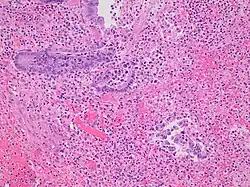

Pathology diagnosis of appendicitis can be made by detecting a neutrophilic infiltrate of the muscularis propria.

Classification of acute appendicitis based on gross pathology and light microscopy characteristics[80]

Pattern Gross pathology Light microscopy Image Clinical significance

Acute intraluminal inflammation None visible

• Only neutrophils in the lumen

• No ulceration or transmural inflammation

Probably none

Acuta mucosal inflammation None visible

• Neutrophils within the mucosa, and possibly in the submucosa

• Mucosal ulceration

May be secondary to enteritis.

Suppurative acute appendicitis May be inapparent.

• Dull mucosa

• Congested surface vessels

• Fibropurulent serosal exudate in late cases

• Dilated appendix

• Neutrophils in the mucosa, submucosa, and muscularis propria, potentially transmural.

• Extensive inflammation

• Commonly intramural abscesses

• Possibly vascular thrombosis

Can be presumed to be the primary cause of symptoms

Gangrenous/necrotizing appendicitis

• Friable wall

• Purple, green, or black color

• Transmural inflammation, obliterating normal histological structures

• Necrotic areas

• Extensive mucosal ulceration

Will perforate if untreated